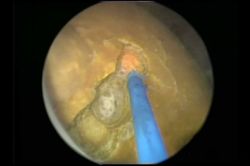

Kahta’da ağrısız endoskopi hizmeti

Böbrek taşı tedavisinde lazer rahatlığı